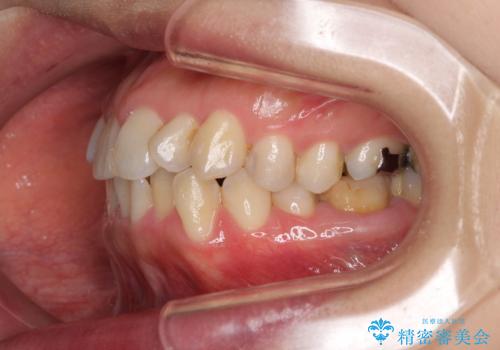

- 前歯の捻れを気にして来院された患者様です。

上顎前歯が捻れて前方に飛び出しており、下顎前歯もそれに沿うようにデコボコとなっていました。

IPR(歯と歯の間を削る処置)によりスペースを獲得して上下前歯のデコボコを改善し、インビザラインにて矯正治療を行うこととしました。

捻れていた前歯の形態が、先端が欠けていたり、一部むし歯処置により左右非対称の形態となっていたため、なかなかゴールが定まらず、治療期間がかかってしまいました。